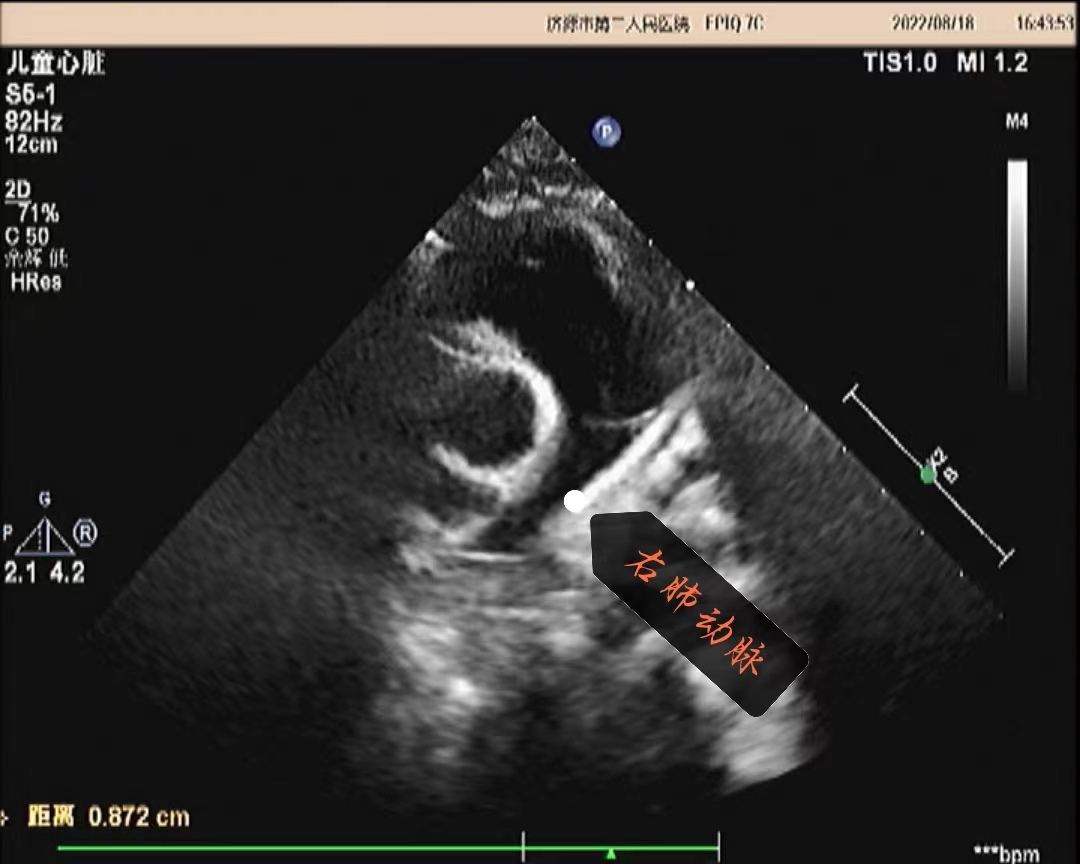

超声所见:各房室大小正常,肺动脉主干内径增宽,约20mm,左右肺动脉内径分别约10mm、8.7mm,左肺动脉起始于主肺动脉的右侧并向左侧走行,右肺动脉起始于主肺动脉左侧向右走行。主动脉内径正常,搏动好。各瓣膜回声正常,肺动脉瓣开启可,关闭欠佳,余瓣膜启闭自如。房室间隔连续完整,室壁厚度及运动收缩幅度正常。CDFI:主肺动脉及左、右肺动脉前向流速增快,主肺动脉峰值流速:2.5m/s、左肺动脉峰值流速:2.2m/s、右肺动脉峰值流速:1.7m/s;肺动脉瓣口探及舒张期少量返流。

超声提示:1.左右肺动脉交叉 2.肺动脉主干内径增宽 3.肺动脉主干及左、右肺动脉前向流速增快 4.肺动脉瓣少量返流

(肺动脉主干及右肺动脉)